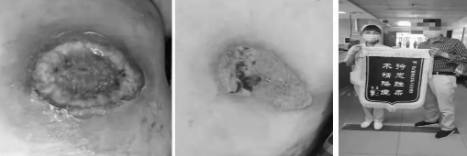

这样的案例,不胜枚举。患者王某某,全身多处反复溃疡发作多年,各地寻医效果不佳,通过他人介绍,于2021年8月和2022年3月前后两次到红河州第三人民医院伤口门诊就诊,护理团队通过不断研究探讨,采取全身免疫治疗+局部激素+自溶清创+“护场法”+湿性敷料治疗坏疽性脓皮病,积累了一定的经验,溃疡两周就能够愈合,患者万分感谢:“咱们三院伤口处理好样的!”